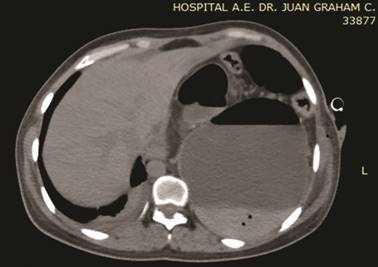

En la TC simple en corte axial, destacó la protrusión del estómago, asas intestinales y grasa mesentérica, a través de un defecto herniario posterior que ocupa hasta un 90% del hemitórax izquierdo, provocando pérdida de volumen del pulmón ipsilateral y atelectasias segmentarias basales derechas (figura 3). En el corte coronal, se identificó un defecto herniario posterior y lateral de aproximadamente 55 mm, además de una importante distensión del estómago, desplazamiento cefálico del bazo y asas intestinales, con compresión y desplazamiento caudal del lóbulo hepático izquierdo (figura 4). Se integró diagnóstico clínico y radiológico de hernia de Bochdalek incarcerada.

Foto: Otorgada por los autores

Figura 3 Tac simple toracoabdominal corte axial. Se aprecia ocupación del hemitórax izquierdo por contenido abdominal con pérdida de volumen y con broncograma aéreo en pulmón izquierdo.